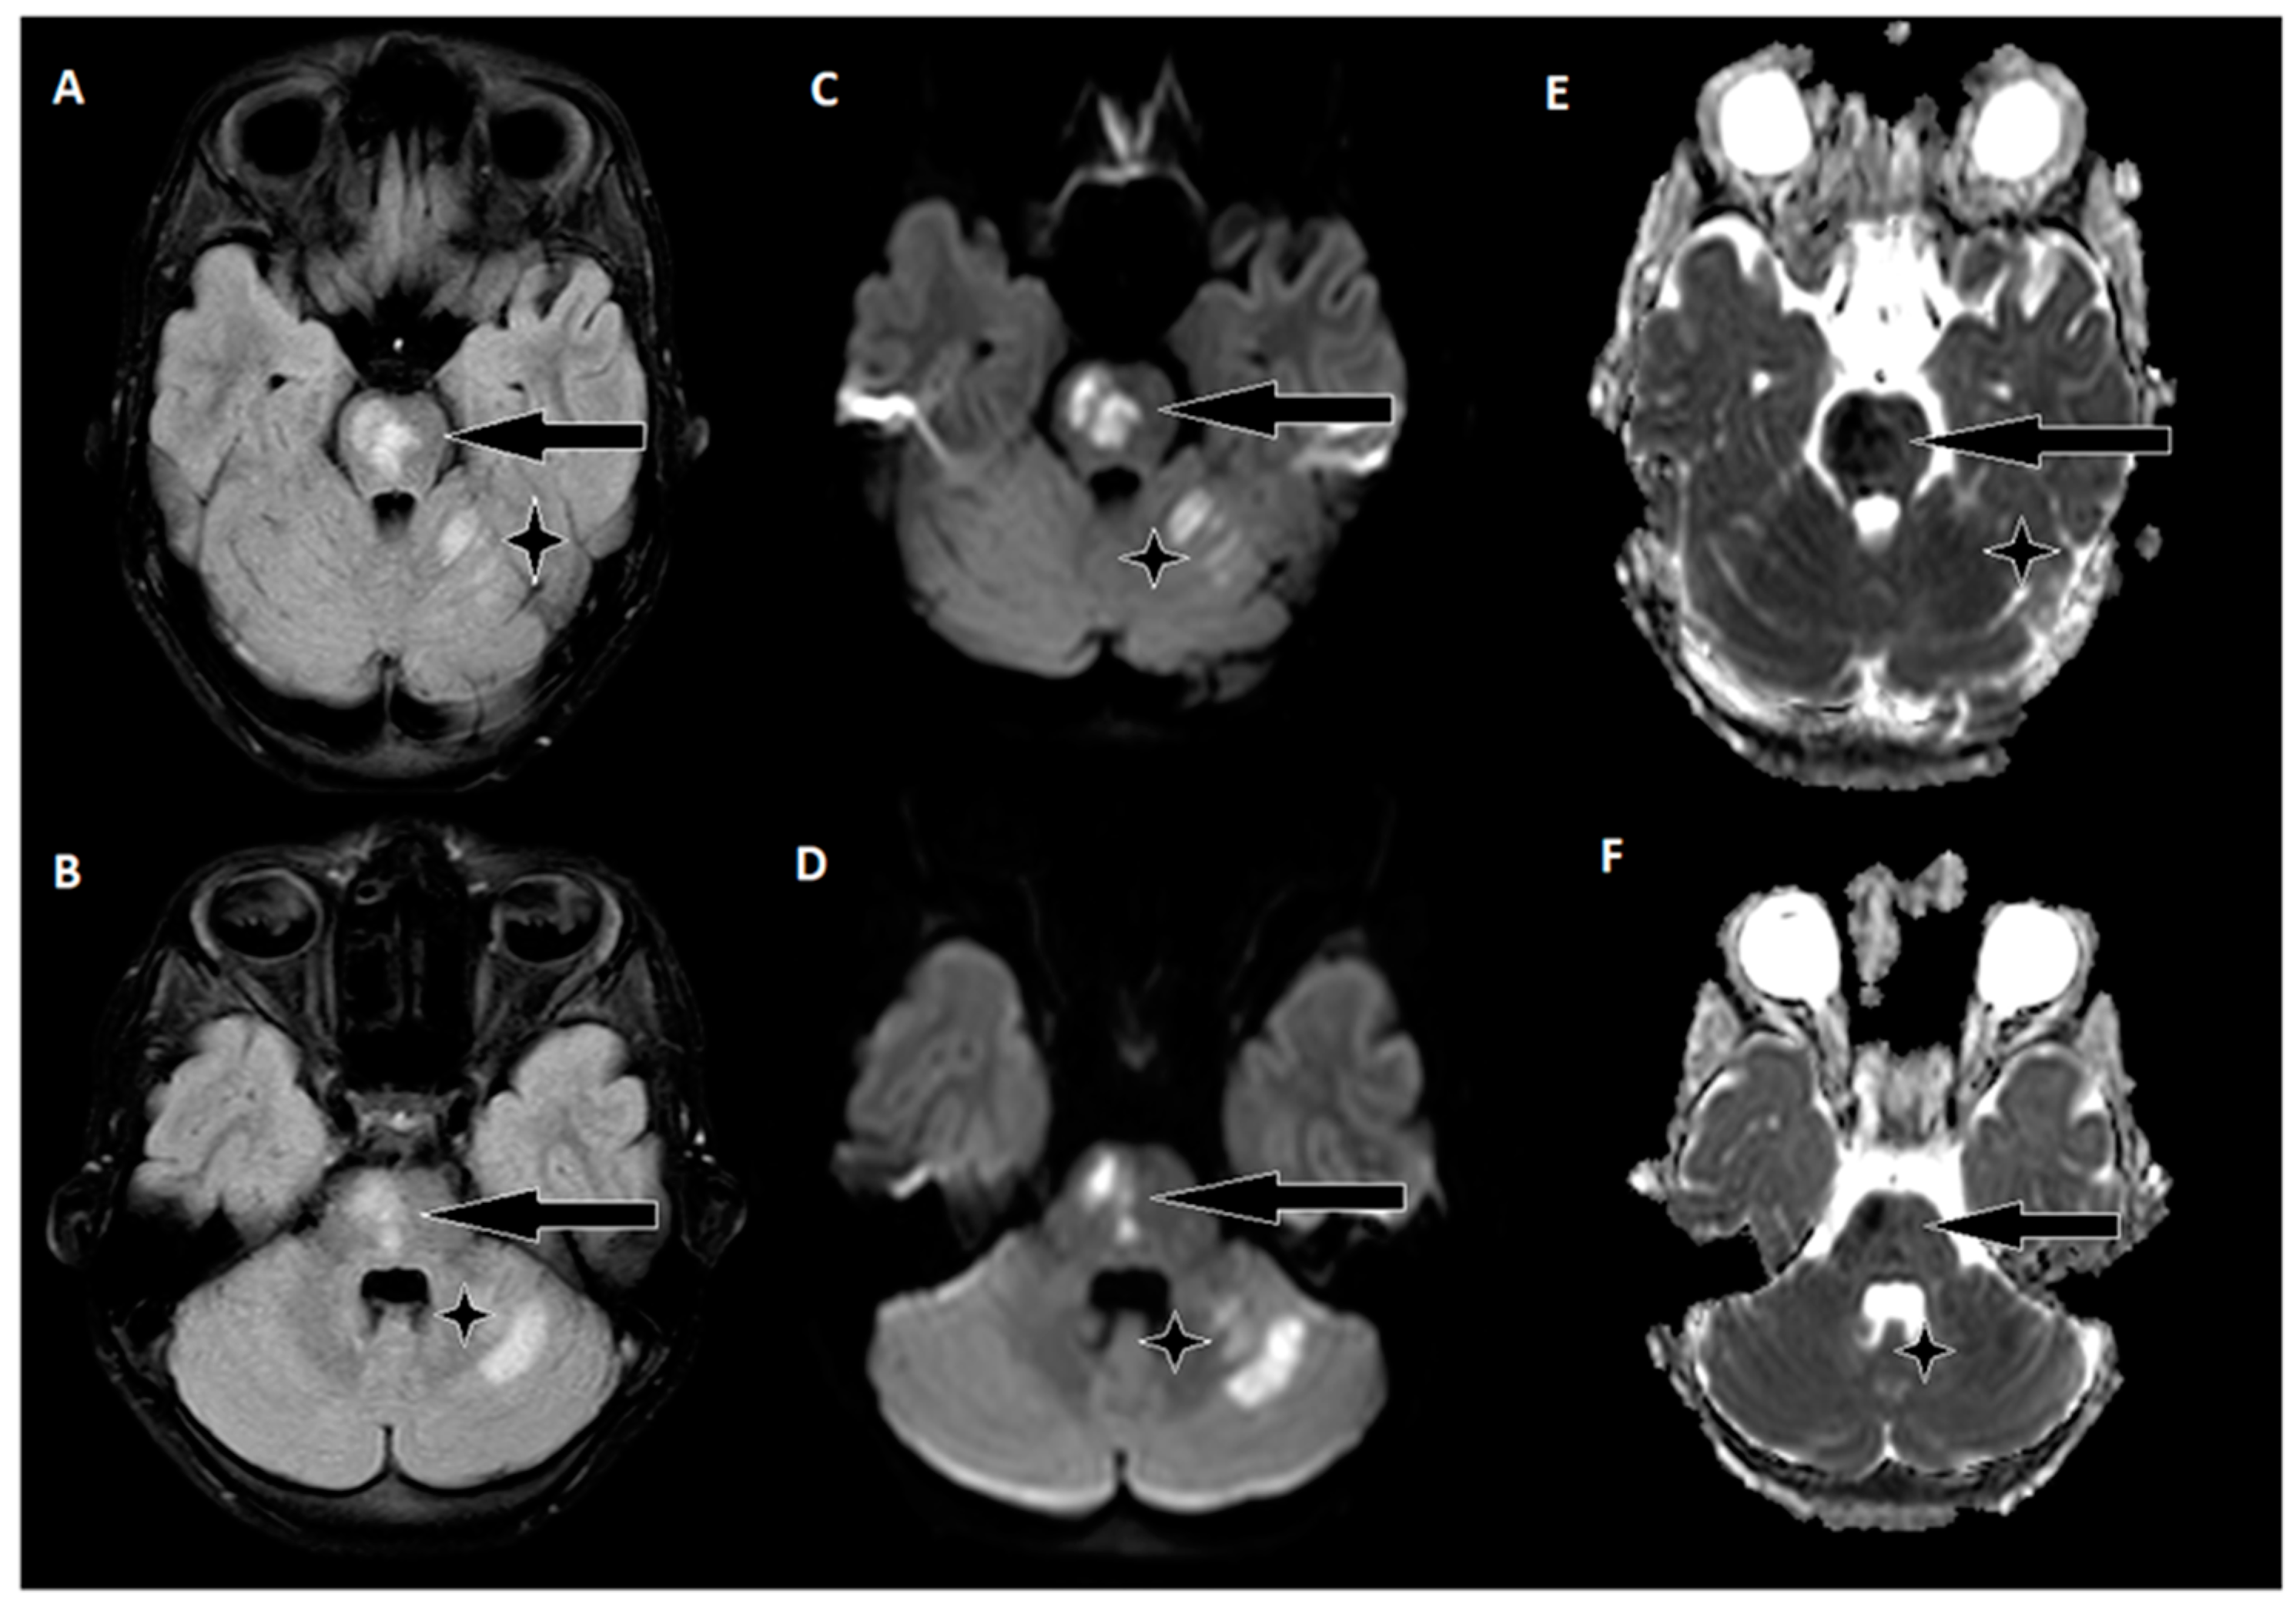

Following 3.5 h and in consultation with a pediatric specialist, the decision was made to transfer the patient to the Children’s Clinical University Hospital for a more comprehensive diagnostic assessment. An emergency magnetic resonance imaging (MRI) was conducted (Figure 2), revealing acute ischemia within the vascularization area supplied by the left posterior inferior cerebellar artery (PICA). Moreover, this MRI also indicated involvement in regions supplied by the left anterior inferior cerebellar artery (AICA) and superior cerebellar artery (SCA). The magnetic resonance angiography (MRA) performed concurrently showed evidence of a thrombus causing occlusion in the distal one-third of the basilar artery (BA). This comprehensive imaging assessment illuminated the extent of the vascular compromise and provided critical information for further evaluation and treatment planning.

Although the MRI revealed significant brain damage, as evidenced by positive findings on FLAIR (fluid-attenuated inversion recovery) and DWI (diffusion-weighted imaging), and despite the elapsed time of approximately 8.5 h from the onset of symptoms, a collaborative decision involving a team of medical specialists including a pediatrician, radiologist, strokologist, and interventional radiologist was made to proceed with EVT as the patient was deemed ineligible for intravenous thrombolysis due to exceeding the time window. This decision was reached despite the limited experience with pediatric strokes, underlining the urgency of the situation.

Figure 2. Emergency magnetic resonance imaging (MRI) before intervention. (A) Changes in the ADC map seen in the left PICA, as well as slightly in the AICA and SCA regions; (B) diffusion-weighted images showing acute changes in the left PICA, as well as slightly in the AICA and SCA regions; (C) MRA showing stop of flow in the distal 1/3 of the basilar artery.